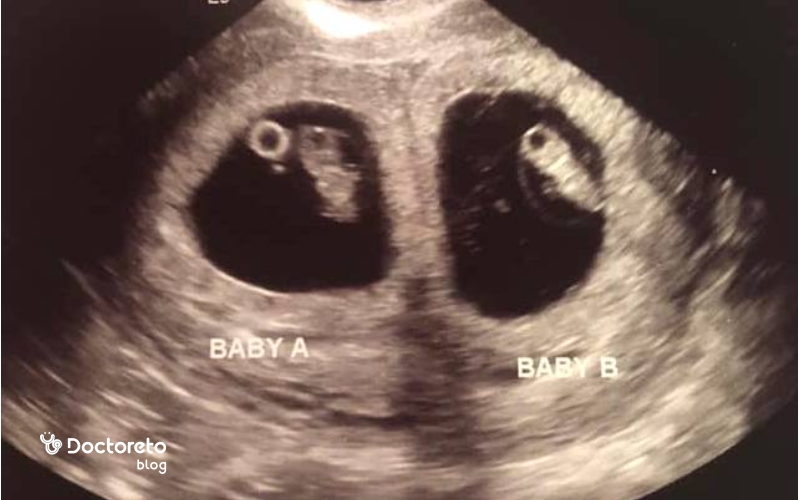

سونوگرافی هفته هفتم بارداری

در سونوگرافی هفته هفتم بارداری معمولاً ساک حاملگی، کیسه زرده و جنین بهطور واضح دیده میشوند. در این مرحله، پزشک رشد طبیعی جنین، محل قرارگیری ساک در رحم و وجود ضربان قلب را بررسی میکند. این سونوگرافی معمولاً از نوع ترانسواژینال است و دقیقترین روش برای تعیین سن بارداری و اطمینان از سلامت اولیه جنین محسوب میشود.

ساک حاملگی بدون جنين در هفته هفتم خطرناک است؟

وجود ساک حاملگی بدون جنین در هفته هفتم بارداری لزوماً به معنای خطر فوری نیست، اما نیاز به بررسی دقیق دارد. در برخی موارد، ممکن است سن بارداری کمتر از محاسبه تقویمی باشد و هنوز زمان کافی برای دیده شدن جنین نرسیده باشد. با این حال، اگر در سونوگرافی تکراری پس از یک هفته همچنان جنینی دیده نشود، احتمال بارداری پوچ (Blighted Ovum) مطرح میشود؛ حالتی که تخم بارور در رحم لانهگزینی کرده اما جنین رشد نکرده است. این وضعیت معمولاً بهصورت خودبهخود یا با مداخله پزشکی پایان مییابد. بنابراین، در صورت مشاهده ساک بدون جنین، پزشک معمولاً آزمایشهای hCG سریالی و سونوگرافی مجدد را برای تشخیص قطعی توصیه میکند.